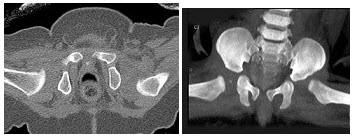

67、单项选择题

男,根据其正常骨盆影像图像,判断其最可能的年龄()

A.5岁左右

B.10岁左右

C.15左右

D.20岁左右

E.25岁左右